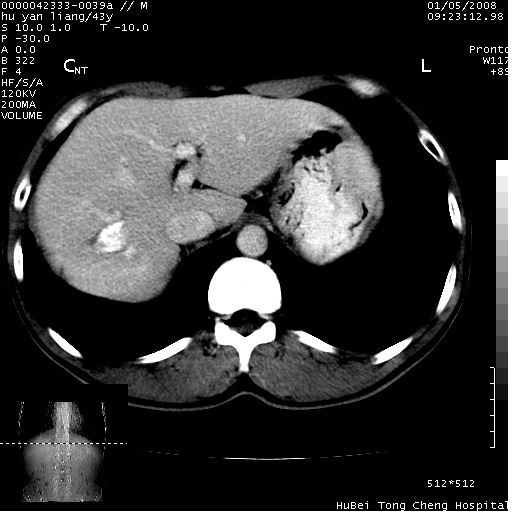

患者 男,43岁。右上腹不适1年余。既往有“肝右叶肝脓肿”病史,经保守治疗后痊愈。

b超提示:1)肝右叶肝内胆管结石。2)肝右叶占位性病变待排。

上中腹部ct轴位平扫+增强扫描(层厚10mm,螺距1.0,重建间隔10mm),图像如下:

肝右上叶偏后方较大团片状钙化灶,支持:肝脓肿后遗改变!

肝右叶后段团块状钙化灶,结合病史考虑肝脓肿痊愈后表现。